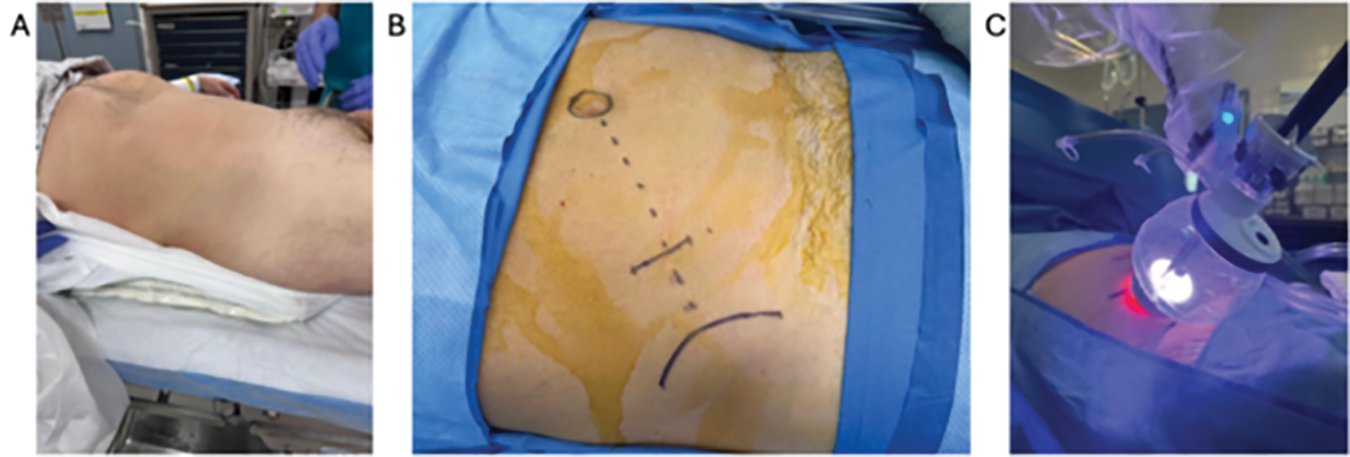

Bilateral sequential compression devices are placed, and a Foley catheter is inserted per urethra in sterile fashion and placed to gravity drainage. The patient is placed in the supine position with a small gel bump to the ipsilateral side (Figure 2A). Tilting the table slightly towards the contralateral side can sometimes aid in having the bowel and peritoneum fall away from the surgical site. The patient’s arms are placed out perpendicular to the axis of the table with appropriate support and padding to all pressure points. The patient is then shaved, prepped, and draped in sterile fashion.

FIGURE 2. Patient positioning. (A) Patient positioned supine with a slight lateral bump on the ipsilateral side. (B) Access is obtained via the supine anterior retroperitoneal access (SARA) approach. (C) The robot is docked through the balloon floating dock into the surgical incision

We utilize the low or supine anterior retroperitoneal access (SARA) technique.2 An approximately 3 cm skin incision is created in a mini-Gibson style, two fingerbreadths medial to the anterior superior iliac spine (ASIS) and towards the umbilicus. Alternatively, the incision can be placed 2 fingerbreadths superior to the ASIS, which can help avoid entry into the peritoneum (Figure 2B). Dissection is carried down through Camper’s and Scarpa’s fascia to the external oblique fascia. The fascial layer is incised in line with its fibers, and blunt dissection is used to separate the external and internal oblique muscles and finally the transversalis muscles to enter the retroperitoneum using a relatively lateral trajectory. The fascial incision can be made slightly longer than 3 cm and slightly more superior to the skin incision. The fascia is aggressively stretched with a blunt clamp to avoid creating a limiting keyhole-shaped entry into the retroperitoneum. Using a finger sweeping motion, blunt dissection is used to develop the retroperitoneal space by pushing the retroperitoneal contents medially until the quadratus lumborum and psoas muscles are palpated deeply. This is best achieved by guiding the finger and palpating the underside of the pelvic bone inferiorly and then gently sweeping all the peritoneal contents medially. Care should be taken to avoid peritoneal entry, the risk of which is increased by excessive sweeping medially. Inadvertent peritonotomies should be immediately closed primarily when recognized to avoid insufflation of the peritoneum when docking the robot, as this can limit the working space within the retroperitoneum.